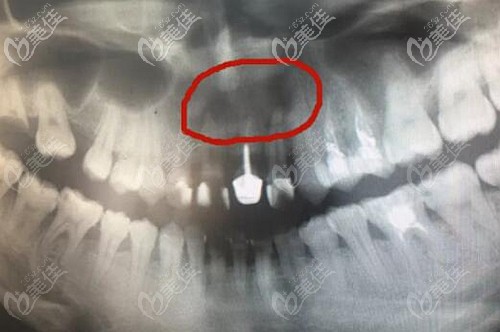

(牙根尖囊腫)

我這牙根尖囊腫因?yàn)闋砍兜窖栏容^多,再加上已經(jīng)出現(xiàn)了牙槽骨吸收的情況,所以就只能做手術(shù)了!

術(shù)中就先做了根管治療及充填,之后才做了囊腫切除及植骨手術(shù),反正整體是比較繁瑣的,但效果確實(shí)是比較理想的,起碼現(xiàn)在恢復(fù)后牙齒沒有再疼的受不了了。